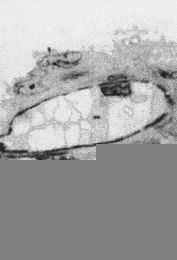

Microscopía electrónica

La observación al microscopio de barrido de la pared vascular en el grupo control muestra células endoteliales de forma alargada, bien organizadas en una única dirección y con una superficie relativamente rugosa. En algunas células, se observaron vesículas de secreción de forma redondeada (Fig. 4A). En las venas umbilicales de gestaciones con PE, la presencia de células con protusiones o vesículas era más frecuente, asimismo, el número y tamaño de estas vesículas era superior, dando al endotelio un aspecto rugoso y desorganizado (Fig. 4B). La orientación celular está menos definida, el endotelio aparece desorganizado y se pierde el aspecto de alineación (Fig. 4D). Era frecuente encontrar zonas erosionadas (desendotelización) y se observa un incremento de las estructuras fibrosas y de los coágulos (Figs. 4C, 4E y 4F). En algunas células, puede apreciarse una depresión superficial (Fig. 4D) y, en las paredes de los vasos, se detectaron vesículas, probablemente lipídicas, coincidiendo con las zonas de mayor erosión endotelial (Fig. 4E).

FFigura 4.Vena umbilical procedente de gestación sin complicaciones (A) y complicadas con preeclampsia (B-F). Vesículas de secreción (A, flecha). Depresión superficial (D, flecha). Vacuolas lipídicas (E, flecha).

A nivel ultraestructural, otros autores han observado una reducción de la luz de los capilares en gestantes afectas de PE debido al incremento de volumen de las células endoteliales(10,11,13). Nuestros resultados también muestran una reducción en el diámetro de la vena y arterias umbilicales en cordones procedentes de gestaciones con PE. Se ha sugerido que el incremento de volumen citoplasmático y de los orgánulos celulares podría ser la causa de la lesión endotelial y su posterior descamación. Las anomalías observadas, especialmente en las mitocondrias, sugieren la existencia de una alteración metabólica sistémica en la PE, y son coincidientes con la demostración de alteraciones genéticas que afectaran a algunos de los genes de la cadena respiratoria mitocondrial(12,26).